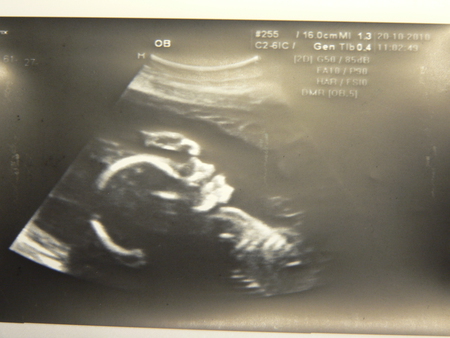

На фотке по УЗИ 26 неделек - Улыбаемся и машем))))